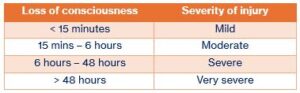

When someone has a brain injury, they might lose consciousness for a short time, a long time, or not at all. This simply means how long they were “out” or unaware of what was happening.

The length of time someone is unconscious is one of the clues doctors use to understand how serious the injury may be. Some people wake up quickly, some take longer, and every person’s recovery is different.